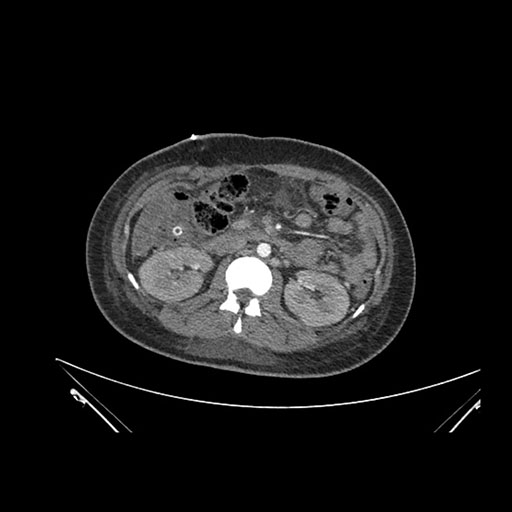

Imaging Analysis

Look through the patient's CT scan to identify any areas of concern for the necessary procedure.

Axial Arterial

Axial Venous

Based on initial findings, which issue(s) would you be most concerned about?